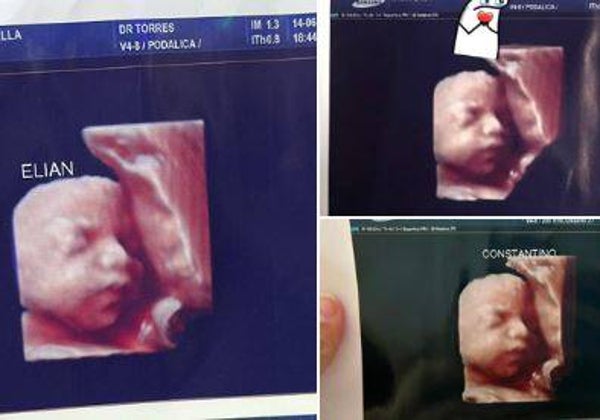

«¡Tengo la misma foto!»: embarazadas denuncian en redes sociales que las estafaron con la ecografía 5D

A. CabezaAl menos una decena de familias creen que las estafaron con las pruebas que les hizo una clínica del norte de Argentina